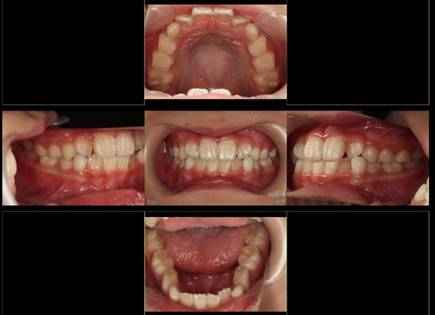

インビザラインによる矯正症例2 22歳女性

治療開始時。正中離開と過蓋咬合がありました

治療途中 5か月後

治療終了 治療開始後7か月